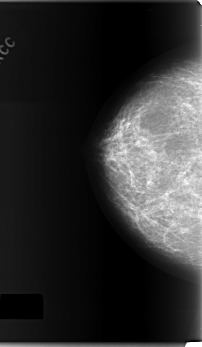

C_0165_1.RIGHT_CC

RIGHT_CC LINES 5896 PIXELS_PER_LINE 3424 BITS_PER_PIXEL 12 RESOLUTION 50 NON_OVERLAY